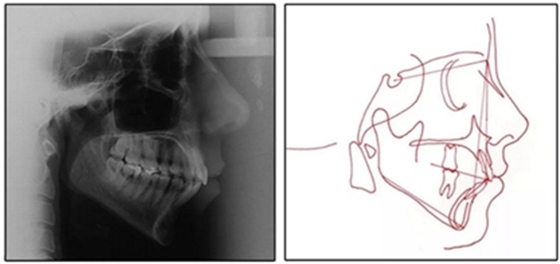

患者是一名39歲的白人婦女,病史不明。她主訴是她的右側(cè)顳下關(guān)節(jié)有不適癥狀,并希望改善她的笑容。她有一個(gè)對(duì)稱的臉型和一個(gè)II類2分類的微笑。她的側(cè)貌是凸的,90°的鼻唇角和骨性下頜骨發(fā)育不足??趦?nèi),上頜中線與面部重合,但下頜中線向右側(cè)偏移5mm;存在6mm的深覆蓋。她的兩側(cè)都是I類磨牙關(guān)系,左側(cè)是I類尖牙關(guān)系,右側(cè)是完全的II類尖牙關(guān)系。下頜右側(cè)第二前磨牙先天性缺失(圖1和圖2)。最初的全景片顯示了足夠的骨質(zhì)水平和全部的第三磨牙(圖3)。治療前的頭影測(cè)量片片和相應(yīng)的頭影測(cè)量圖(圖3)證實(shí)ANB為7°,Wits評(píng)估為6 mm的骨性II類錯(cuò)合(表)。上頜切牙相對(duì)與面部和顱底的位置很好。下頜切牙前傾。診斷為II類2分類錯(cuò)合畸形,伴有骨性下頜發(fā)育不足,右側(cè)顳下頜關(guān)節(jié)癥狀,下頜中線向右側(cè)偏移5mm,先天性右下第二前磨牙缺失。

圖3. 治療前頭影側(cè)位片,頭影測(cè)量描跡圖和全口X光片

患者決定采用非手術(shù)治療方法,側(cè)貌沒(méi)有任何預(yù)期的變化。治療后面部照片(圖5)顯示她改善的微笑和側(cè)貌,包括尖牙保護(hù)合。由于先天性第一前磨牙缺失,右磨牙關(guān)系為III類。治療后牙齒石膏模型(圖6)顯示實(shí)體牙齒交錯(cuò)排列情況,并且全景X線片顯示可接受的牙根平行度而且沒(méi)有牙根吸收表現(xiàn)(圖7)。最終的頭影測(cè)量片(圖7)證實(shí)了面部評(píng)估,并且描跡圖顯示深覆蓋的改善,同時(shí)保持上頜切牙位置并通過(guò)測(cè)量ANB角度和Wits評(píng)估改善骨性II級(jí)關(guān)系(表)。治療前后的疊加圖顯示由于下頜切牙前傾的增加改善了下唇平衡(圖8)。如相關(guān)治療計(jì)劃所預(yù)測(cè)的那樣,B點(diǎn)出現(xiàn)。A進(jìn)行牙科錐形束計(jì)算機(jī)斷層掃描以記錄下頜前牙區(qū)的骨質(zhì)變化。如預(yù)期的那樣,由于治療導(dǎo)致該區(qū)域的骨量增加(圖9)。